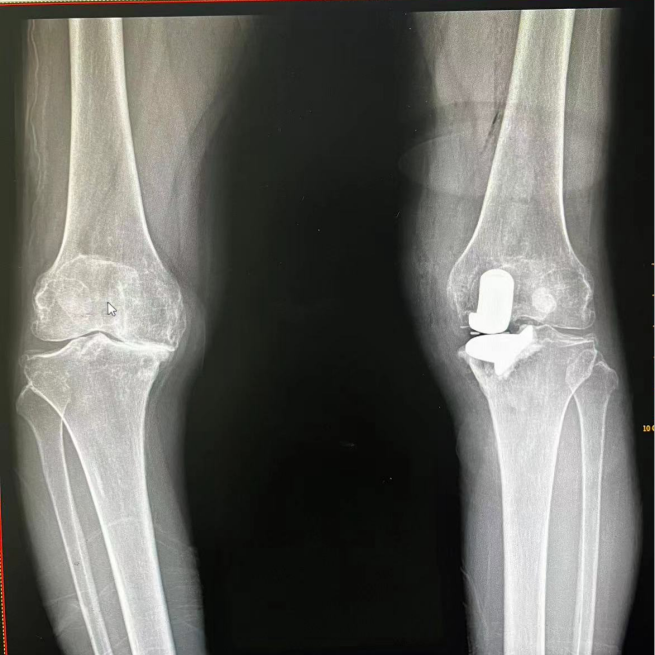

▲莫阿姨术前X线片

66岁的莫阿姨(化名),反复双膝关节疼痛、活动不利20年,伴关节弹响,行走、上下楼梯及深蹲时加重,经多年反复保守治疗未见好转,至今已严重影响生活质量,于是莫阿姨来到该院骨伤科就诊。骨伤科施能槐主任医师接诊后,详细询问病史及查体,诊断为双侧膝关节骨性关节病(重度),目前左膝疼痛为主,建议行左膝关节单髁置换术。患者及家属给予骨伤科团队充分的信任,希望通过手术解决谢阿姨多年的疼痛困扰。骨伤科团队经过术前检查及准备,在施能槐副院长带领下顺利完成左膝关节单髁置换手术。